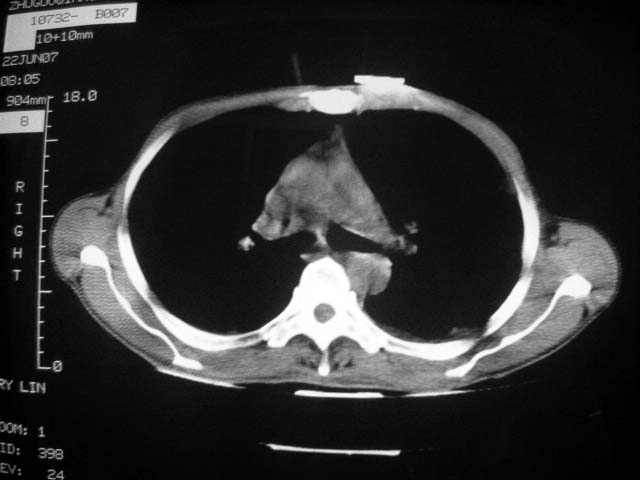

标题: CT7988D:近期图像 出乎意料!

从ct7988c 至今未用任何抗生素及抗痨药,维持保肝治疗。患者低热、咳血渐消失。

07年6月22号复查

前几次大家认为是转移癌,但此次复查病灶却明显吸收好转,不支持诊断。请大家讨论。[emb10]